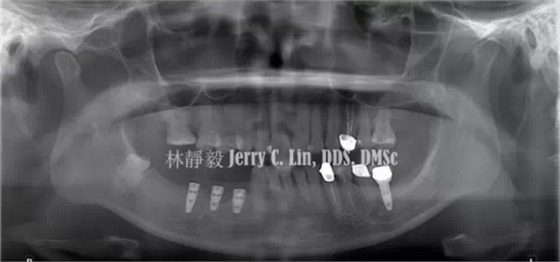

案例在植牙治療完成兩年后,45位置的植體發(fā)生種植體周圍炎(peri-implantitis)如圖1、圖2,約有9個螺紋處的齒槽骨遭到破壞。

QQ圖片20150710145056.png圖1 曲面體層片可見45位置發(fā)生種植體周圍炎

術(shù)后曲面體層片仍可明顯看出牙槽骨破壞的型態(tài)(圖9),此乃因FDBA在骨再生之前顯示透光度較低,藉此追蹤X光上的骨質(zhì)變化,有助于將來判斷骨再生的真實性。

QQ圖片20150710150018.png圖9 曲面體層片可見牙槽骨破壞

術(shù)后半年進行復查,X線片(圖15、圖16)顯示骨再生已達第一螺紋,種植牙周圍約有8~9個螺紋的牙槽骨獲得再生,同時也解決了種植體周圍炎的問題。

圖15 術(shù)后半年曲面體層

圖16 術(shù)后半年根尖片